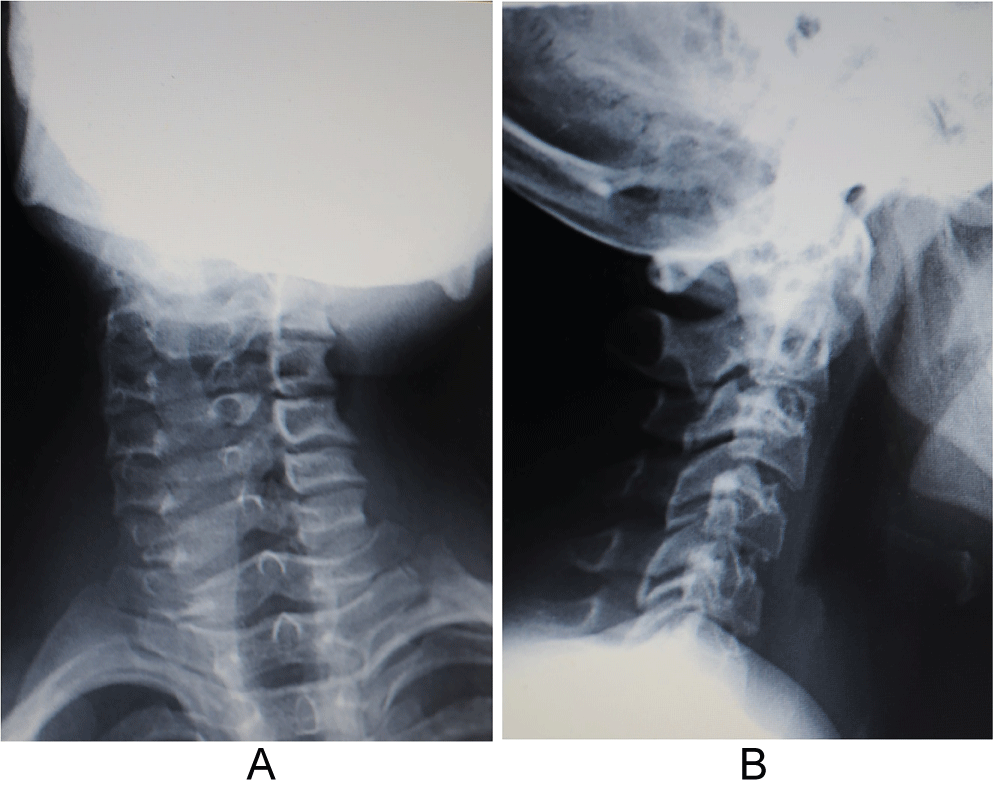

Figure 1: Radiographs of the a) Anteroposterior; b) Lateral cervical spine. No anomalies of segmentation or rachischisis of the vertebral arches were observed. View Figure 1